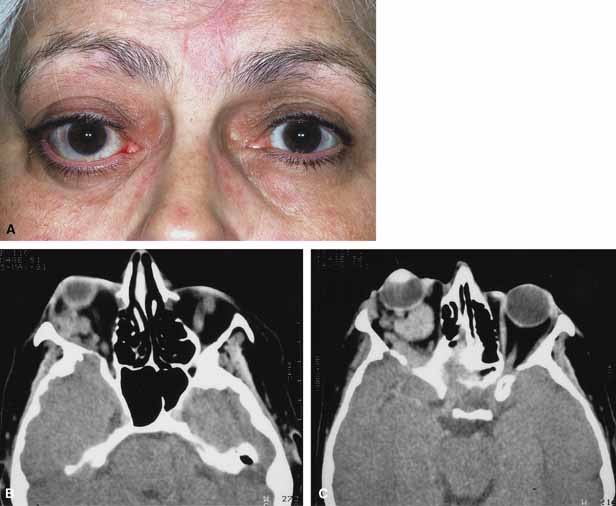

ORBITAL CELLULITIS

Orbital cellulitis is the model for acute inflammation and a major cause of orbital inflammation in adults.2 It is characterized by a rapid development (over 1 to 2 days) of inflammatory signs and symptoms. These include: eyelid swelling, redness, warmth, pain, conjunctival injection, chemosis, proptosis, and mobility impairment with or without reduced vision. These patients generally feel unwell (malaise) and are febrile (Fig. 1A and 1B). The malaise and fever are key features in differentiating cellulitis from a rapid-onset nonspecific orbital inflammation (pseudotumor) and should be obtained from the patient's history.

Fig. 1 A. A 25-year-old patient presented with proptosis, lid swelling, conjunctival chemosis/injection, pain, malaise, and fever. B. Conjunctival chemosis. C. Ethmoid sinus opacification is present with a superior subperiosteal abscess.

The majority of orbital cellulitis is secondary to extension from an adjacent sinus infection (Fig. 1C). Organisms gain access to the orbit directly through the thin ethmoidal bone, through congenital or acquired dehiscences in the thin orbital walls, pass through preexisting orbital foramina, pass retrogradely through the valveless venous orbital system, or along the veins as a periphlebitis. Orbital cellulitis may also be secondary to an endophthalmitis, systemic bacteremia (e.g., after dental work), infection of a nearby skin wound, dacryocystitis, or penetrating trauma.

Progression of the disease process despite appropriate antibiotic therapy suggests abscess formation. Orbital abscesses may be either localized, diffuse, or subperiosteal (Fig. 1C). Subperiosteal abscesses most commonly occur along the medial wall and may expand rapidly, compromising optic nerve function even in the absence of many signs of infection.3–6 Several mechanisms may contribute to visual deterioration including direct optic nerve compression, elevation of the intraorbital pressure, and proptosis causing a “stretch” optic neuropathy. Clinically, the eye typically is displaced away from the subperiosteal abscess, and orbital imaging shows a convex mass adjacent to the involved sinus.

Orbital imaging in the axial and coronal plane should be obtained in all patients suspected of having orbital cellulitis. Computed tomography (CT) is preferred to magnetic resonance imaging (MRI) because the orbital tissues have higher contrast and bone is well visualized. Axial CT views allow evaluation of the medial orbit and ethmoid sinuses, whereas coronal scans image the orbital roof, floor, frontal, and maxillary sinus. A subperiosteal abscess appears as a homogeneous opacification between the orbital wall and the displaced periorbita.6 Contrast agents are not necessary to visualize a subperiosteal abscess.